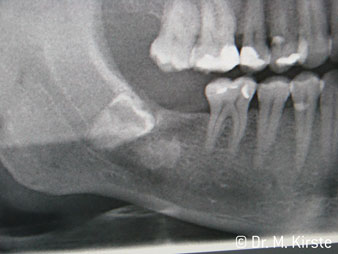

Угол 45° наконечника был выбран специально с учетом широкого круга преимуществ. Коллеги, которые работают в хирургии, и для которых этот наконечник был изначально создан, быстро оценят возможность эффективно работать в очень стесненном пространстве. В частности, при удалении зуба мудрости (рис. 2) не нужно сильно раздвигать мягкие ткани в области щеки (рис. 3). Конструкция головки наконечника в сочетании с небольшим поворотом головки во время препарирования позволяет быстро и безопасно выполнять работу в области задних коренных зубов.

Профессиональная конструкция подшипников внутри головки обеспечивает тихую работу бора; впечатляет атравматичное разделение зуба и корня (рис. 4-9).

Угловой наконечник с углом 45° очень удобно держать в руках. Вы почти сразу отметите, что рабочая головка имитирует угол наклона вашего указательного пальца, поэтому нужное движение легко переносится на пару воображаемых сантиметров параллельно кончику (рис. 1)".